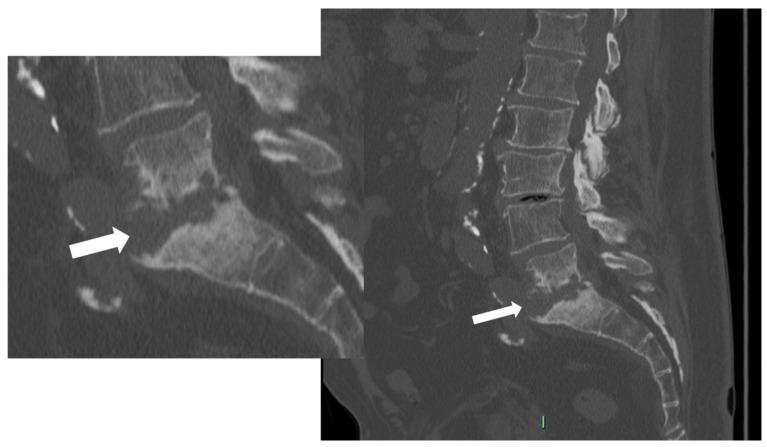

Spondylodiscitis is defined by infectious conditions involving the vertebral column. The incidence of the disease has constantly increased over the last decades. Imaging plays a key role in each phase of the disease. Indeed, radiological tools are fundamental in (i) the initial diagnostic recognition of spondylodiscitis, (ii) the differentiation against inflammatory, degenerative, or calcific etiologies, (iii) the disease staging, as well as (iv) to provide clues to orient towards the microorganisms involved. This latter aim can be achieved with a mini-invasive procedure (e.g., CT-guided biopsy) or can be non-invasively supposed by the analysis of the CT, positron emission tomography (PET) CT, or MRI features displayed. Hence, this comprehensive review aims to summarize all the multimodality imaging features of spondylodiscitis. This, with the goal of serving as a reference for Physicians (infectious disease specialists, spine surgeons, radiologists) involved in the care of these patients. Nonetheless, this review article may offer starting points for future research articles.

脊椎椎间盘炎是由涉及脊柱的感染性疾病所定义的。在过去几十年中,该疾病的发病率持续上升。影像学在疾病的各个阶段都起着关键作用。实际上,放射学工具在以下方面至关重要:(i)脊椎椎间盘炎的初始诊断识别;(ii)与炎症性、退行性或钙化性病因进行鉴别;(iii)疾病分期;以及(iv)为确定所涉及的微生物提供线索。后一个目标可以通过微创程序(例如CT引导下活检)实现,或者通过分析所显示的CT、正电子发射断层扫描(PET)CT或MRI特征进行非侵入性推测。因此,本综述旨在总结脊椎椎间盘炎的所有多模态影像学特征。目的是为参与这些患者护理的医生(传染病专家、脊柱外科医生、放射科医生)提供参考。尽管如此,这篇综述文章可能为未来的研究文章提供起点。